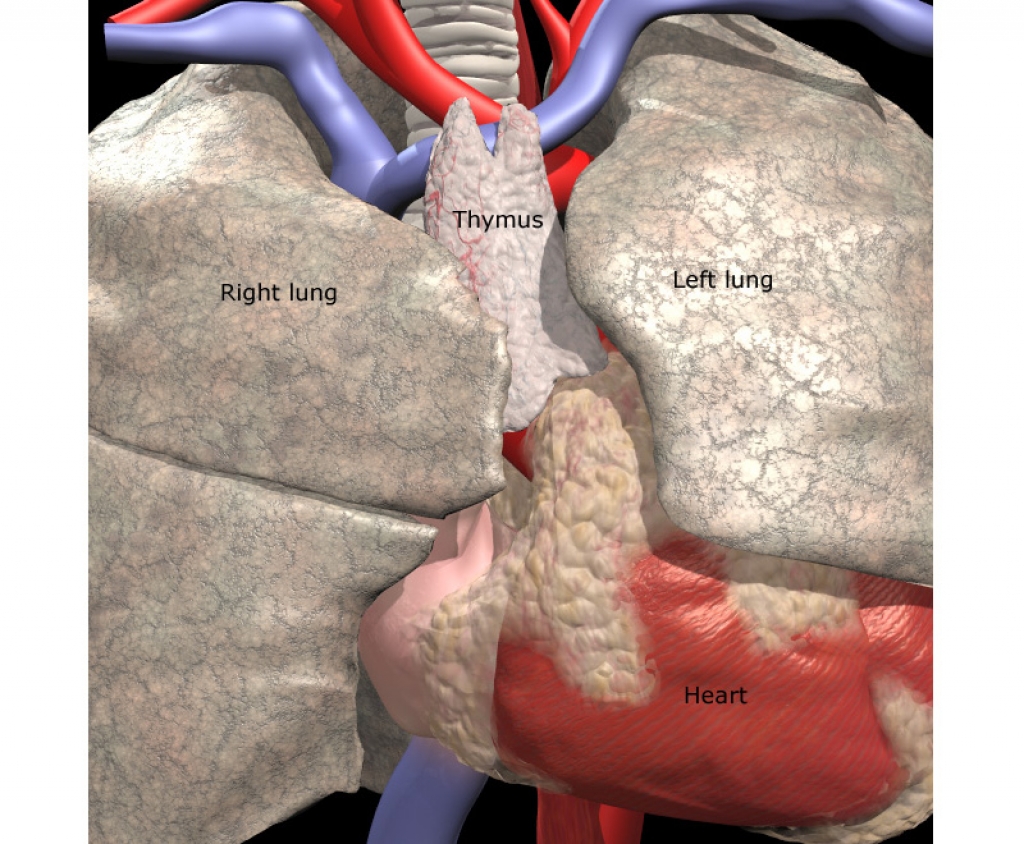

Фотографии вилочковой железы тимуса: структура и функции